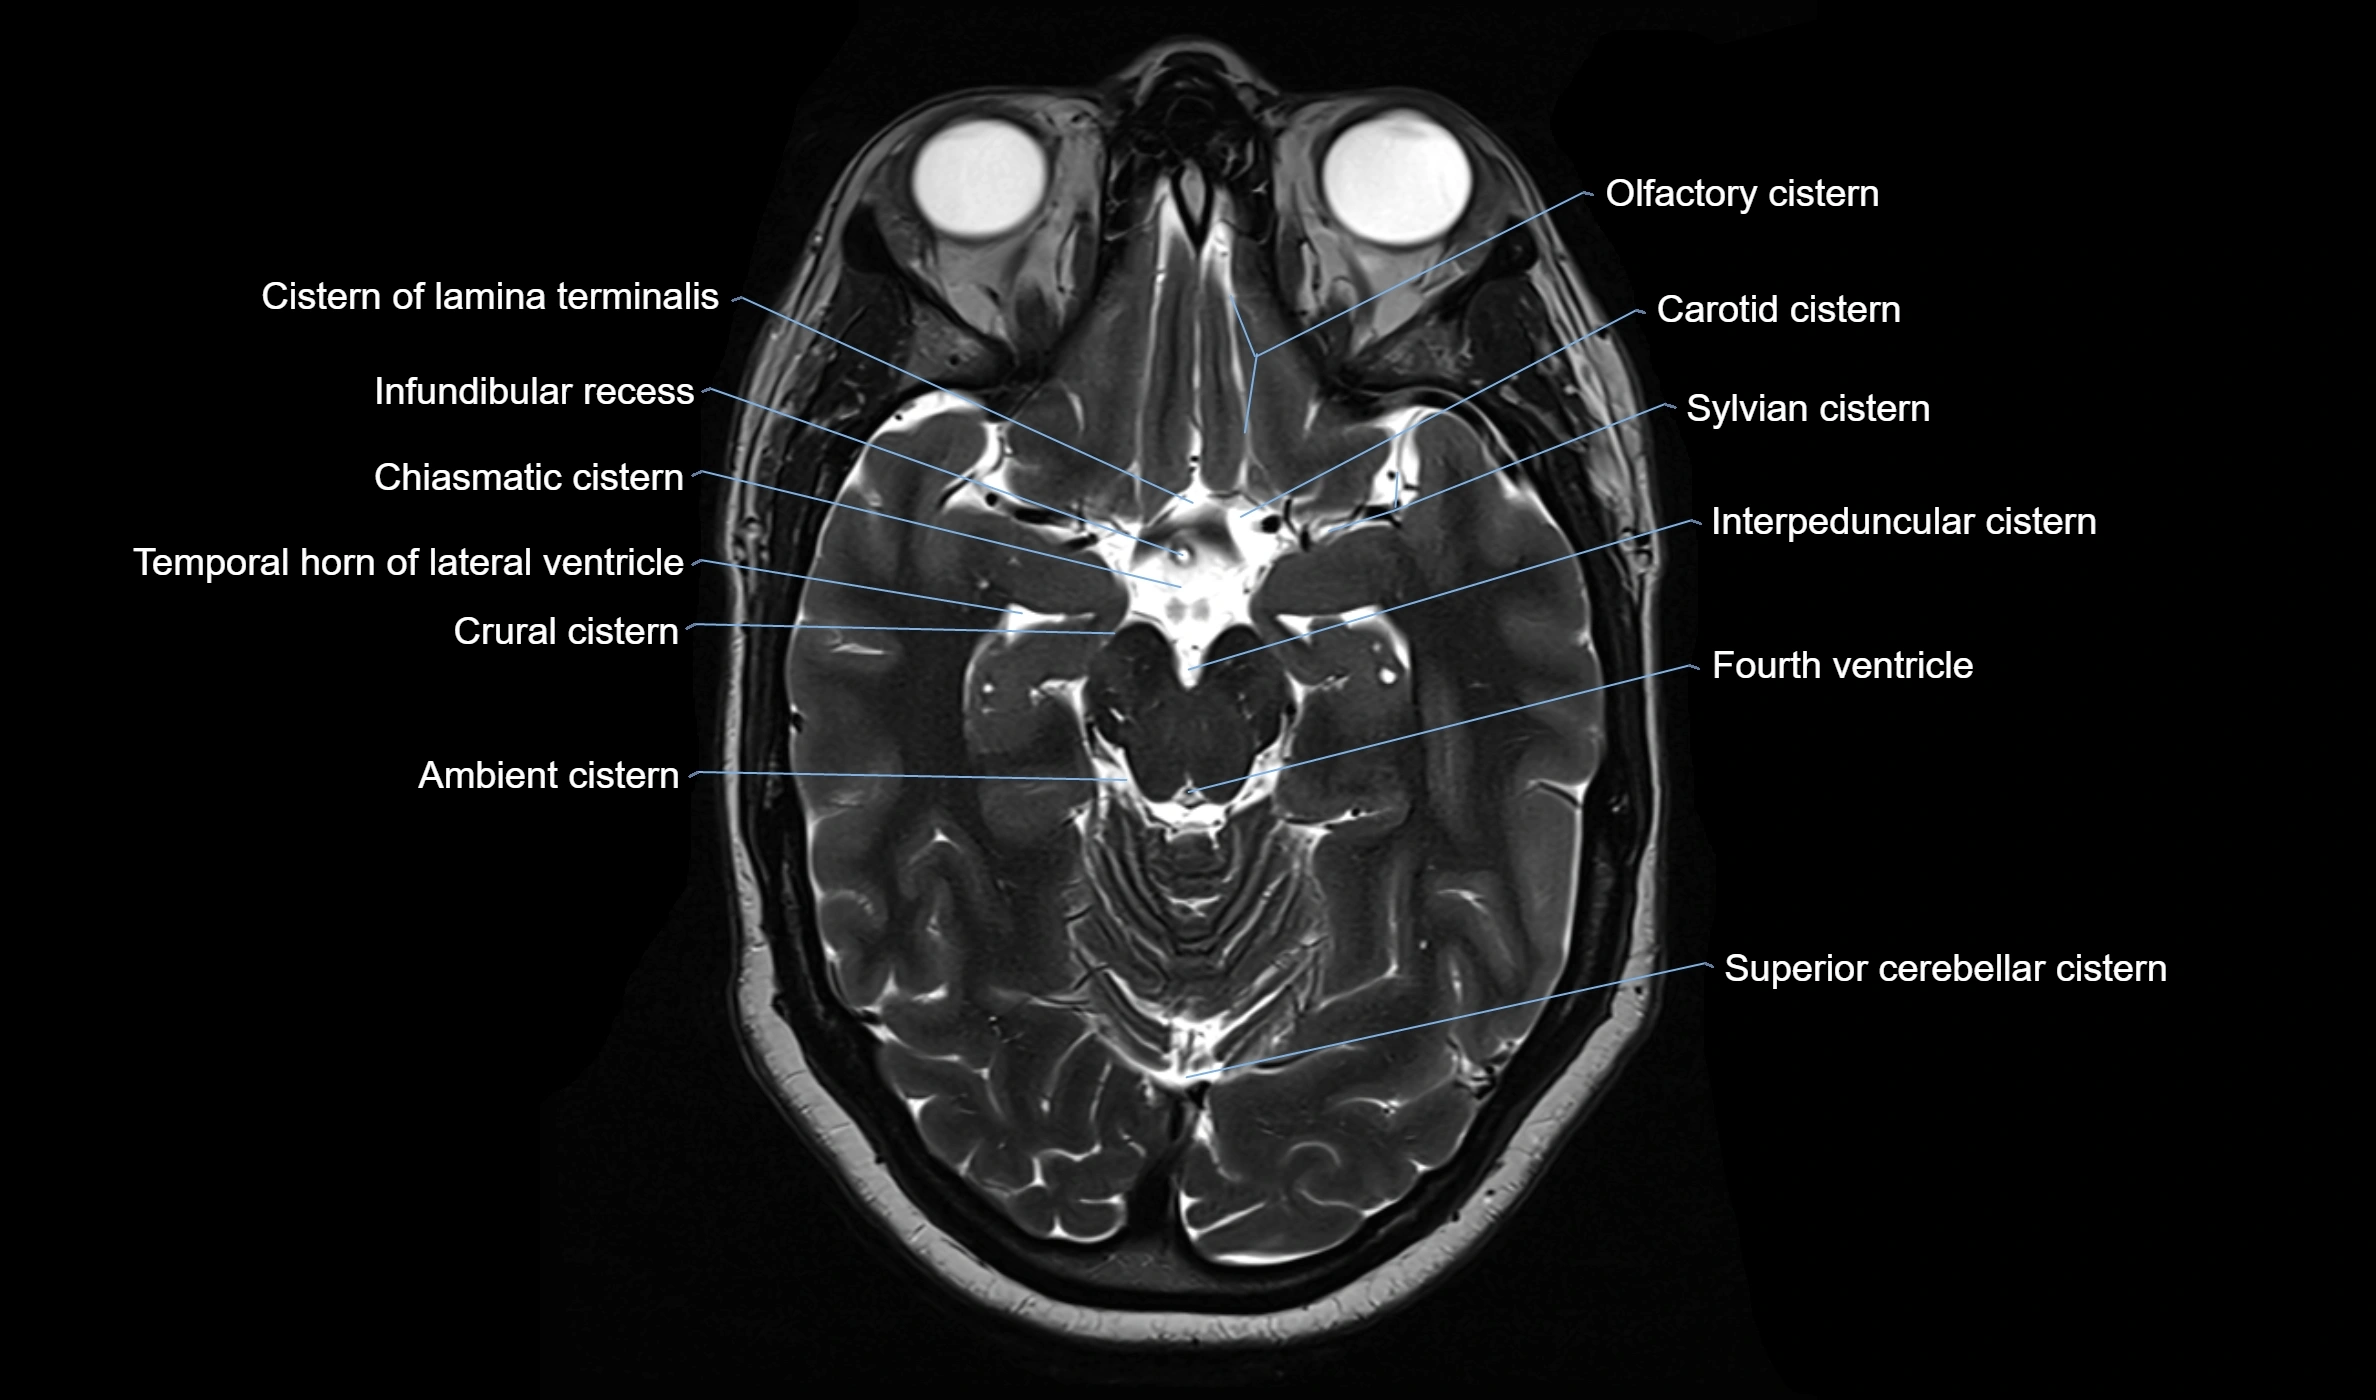

MRI images

image